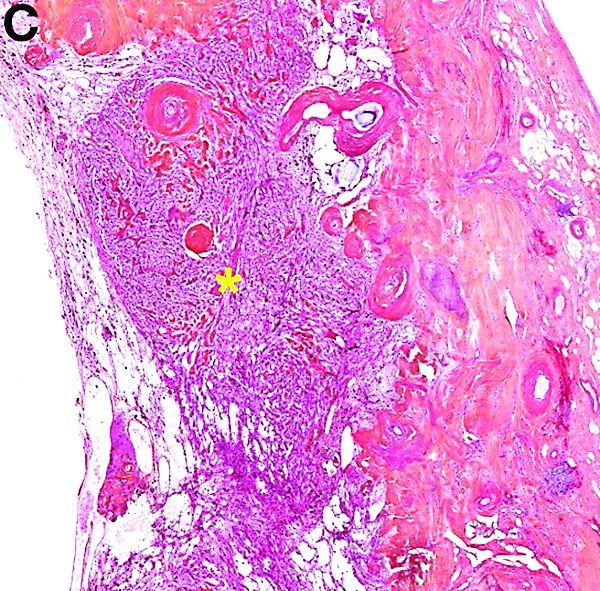

Histologically (Figure C), the fibrous wall contained many large vessels and a small cellular area (star). This area consisted of small nests of moderate-sized monotonous clear cells with normochromatic ovoid nuclei. There was no nuclear atypia and no mitosis. The tumor exhibited an elaborate network of small capillaries. Tumor cells expressed the melanocytic marker HMB45 and smooth muscular actin.